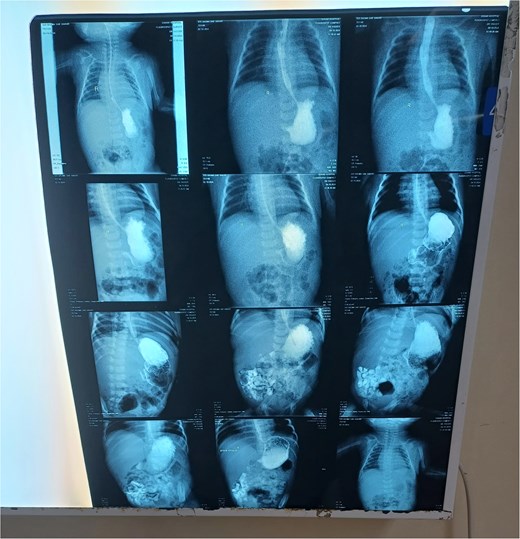

Chest X-ray was normal (Fig. 1). A water-soluble contrast meal was performed (Fig. 2) and the contrast arrested at the gastric antrum for 45 min. Then there was normal opacification of the duodenum and jejunum on follow-up films after 1.15 and 1.3 h. A complementary ultrasound (US) was done along with the contrast study and it showed a thick mucosal fold (4 mm) at the gastric antrum situated 1 cm away and on the left side of the duodenum. The pyloric canal was open and patent and had a normal wall thickness (1.5 mm) excluding hypertrophic pyloric stenosis.

The contrast study done pre-operatively showing the progression of the contrast in the digestive tract of the neonate.

For antral web, an upper gastrointestinal (UGI) series reveals persistent, sharp band-like linear defect in antrum and the “double bulb sign”, with gastric dilatation, and a delay in gastric emptying. The pylorus shows normal thickness and patent lumen. If confused with pyloric stenosis, pyloric muscle thickness is assessed [1]. In our case, the pyloric muscle thickness was normal, and together with the timing of presentation and the radiological signs, GAW was diagnosed by exclusion.